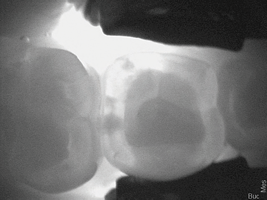

(5.)  Incipient decay on tooth No. 29.

Figure 5

(6)  Incipient decay on tooth No. 20.

Figure 6

A 38-year-old female patient with incipient decay discovered on a transillumination caries detection device image (Figure 5 and Figure 6) presented for her bi-annual hygiene visit. The doctor was considering whether to treat the decay with a restoration or to "watch it." He decided that instead of monitoring the lesion, he could treat it with silver diamine fluoride, possibly halting the decay and hardening the lesion. The patient was informed of the possibility the decay would turn black; however, the decay process could halt, and she would not need a filling in the future. She was pleased at the prospect her tooth would remain intact without needing restorative treatment. After signing the consent form, she opted for treatment that day in the hygiene visit. She was appointed for one week later for the re-application of the silver diamine fluoride and advised that it may need to be reapplied one to two times per year.